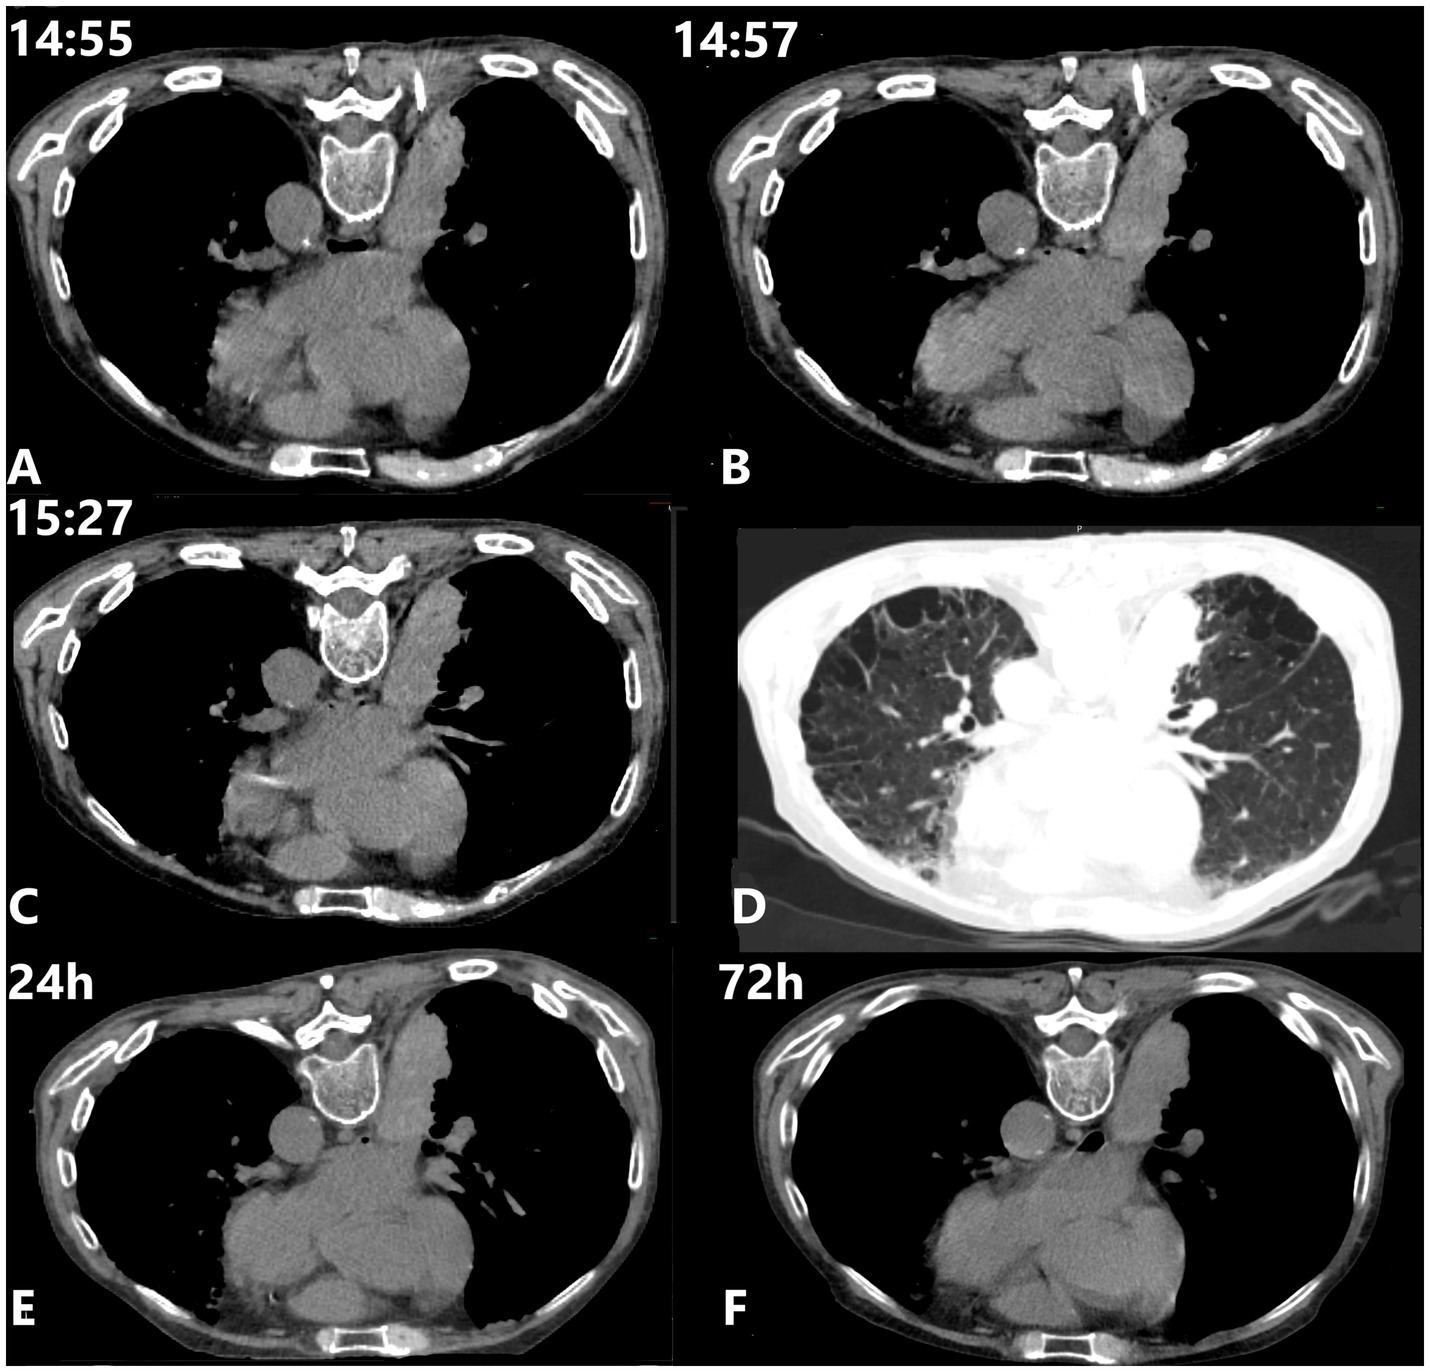

Intercostal artery (ICA) injury during CT-guided percutaneous transthoracic needle biopsy (PTNB) is a rare but potentially severe complication. This case report describes a cautious approach for detecting and managing suspected ICA injury using a coaxial needle system. During PTNB in a 71-year-old male with lung cancer, ICA injury was detected through blood aspiration during needle withdrawal. Management involved immediate cessation of withdrawal, slight needle advancement for mechanical hemostasis, and serial monitoring, achieving hemostasis without requiring additional invasive interventions. Literature review of cases from 2018 to 2024 revealed that current management approaches vary based on severity, with a 30% mortality rate among reported cases. Most ICA injuries are detected post-procedurally rather than intraoperatively. Traditional interventions range from conservative treatment to transcatheter arterial embolization (TAE) or thoracotomy. This approach suggests a potential stepwise method for managing suspected ICA injury that might reduce complications and minimize the need for invasive interventions. As a single case report representing hypothesis-generating evidence, this observation requires further validation through collaborative experience from other operators when similar circumstances arise. The case demonstrates an exploratory approach for managing ICA injury during PTNB, particularly relevant in resource-limited settings where interventional radiology services may not be immediately available.